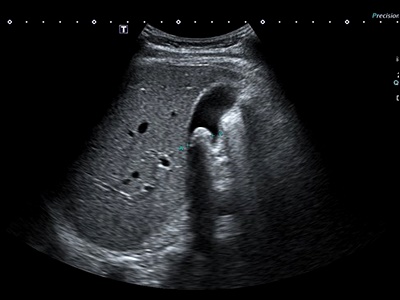

의사는 담낭염을 진단하기 위해 다양한 검사를 시행할 수 있습니다. 가장 일반적인 검사는 혈액 검사와 초음파 검사입니다. 혈액 검사를 통해 염증 마커나 감염 여부를 확인할 수 있으며, 초음파 검사를 통해 담낭의 상태와 담석의 유무를 확인할 수 있습니다. 추가적으로 담도 조영술, CT 스캔, MRI 등의 검사도 시행될 수 있습니다.